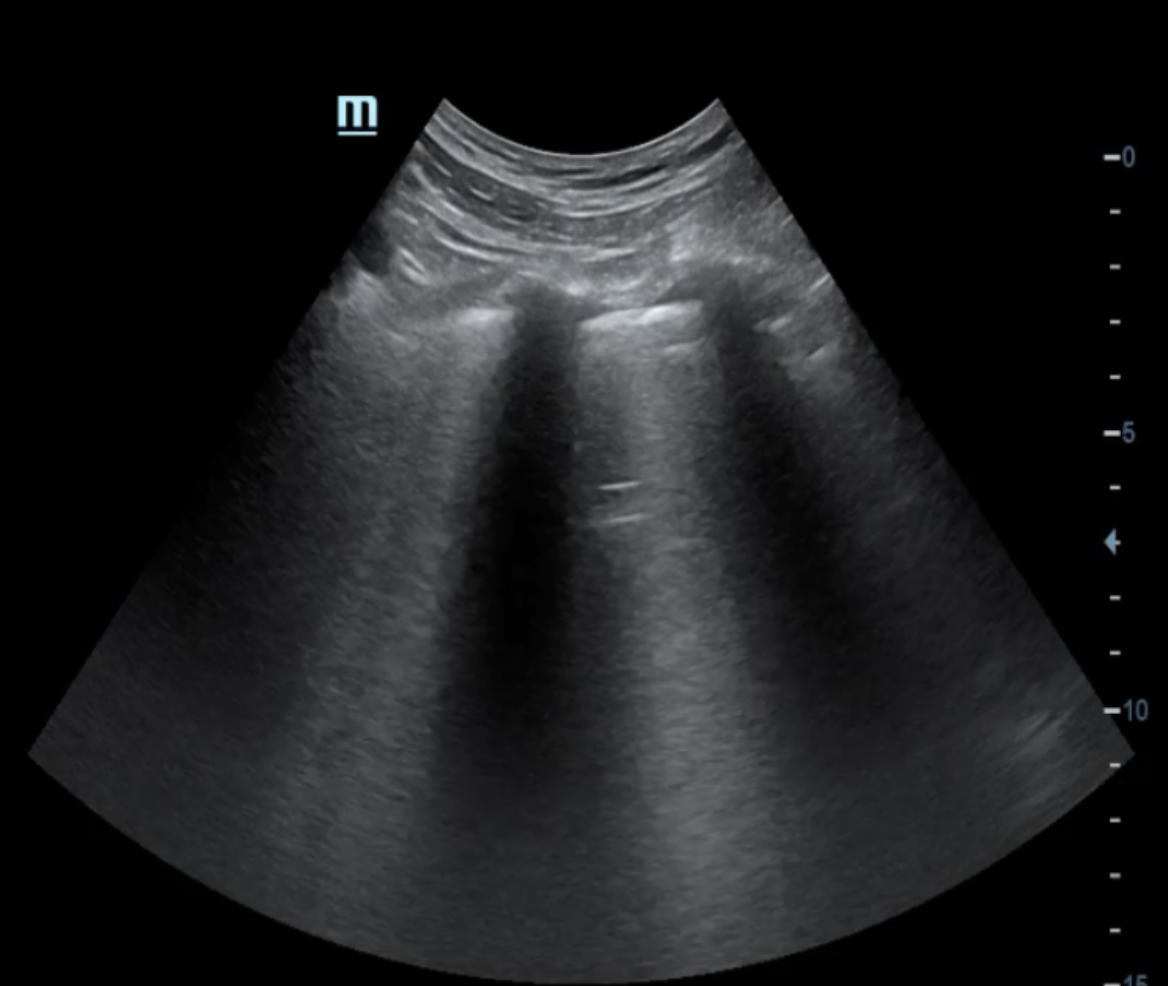

A la exploración ecográfica pulmonar se objetivan líneas B en ambos campos anteriores y superiores, así como derrame pleural bilateral, orientando la causa de la disnea hacia la insuficiencia cardíaca.